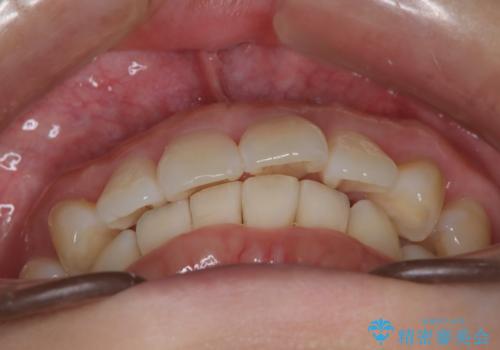

インビザライン ライトパッケージによる部分矯正治療 下の前歯のみの歯並び改善

- インビザライン ライトパッケージパーシャル(下顎のみ)

- 下の前歯の歯並びのみの改善をご希望されました。

インビザライン ライトパッケージ下顎のみ(1枚~14枚まで)での治療を行なっていきました。

マウスピース枚数 初回14枚 + 追加13枚

概ね7ヶ月で治療完了しました。

インビザラインのライトパッケージでは14枚までという枚数制限がありますが、限られた枚数の中で当院独自の工夫を随所に盛り込み、狙い通りの治療結果が得られました。